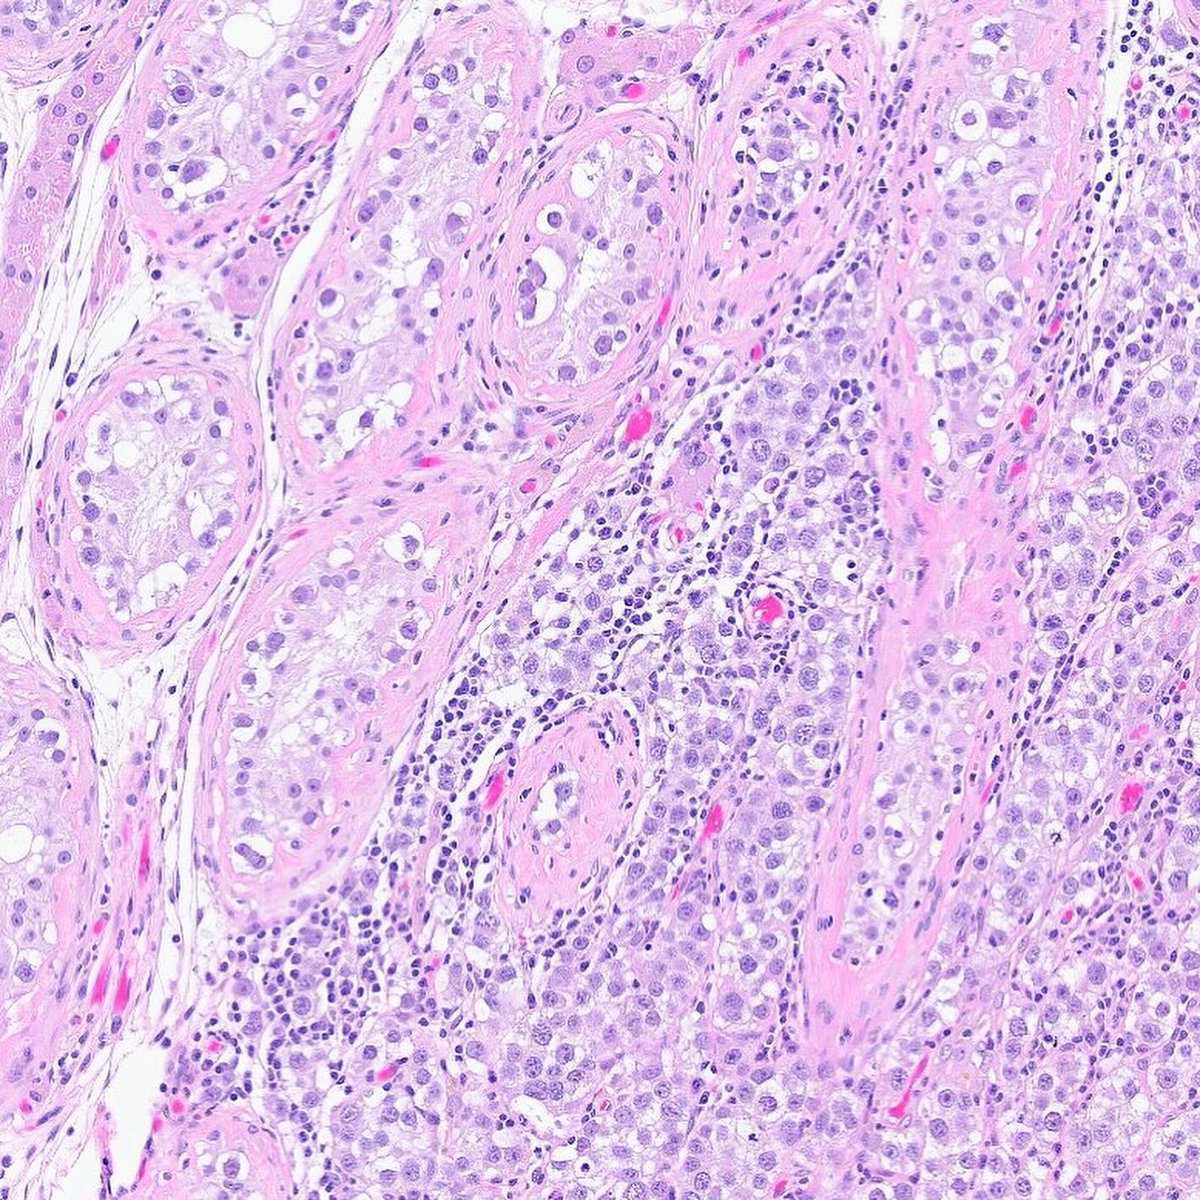

#OpenAccess! Timely recognition of TFE3-rearranged renal cell carcinoma’s distinct cytomorphologic and histomorphologic features is essential for accurate diagnosis and effective treatment.